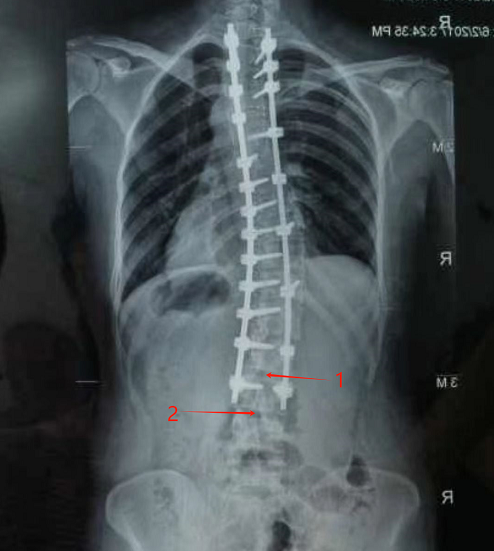

术前,吴强仔细阅读了薛女士的影像学检查结果,发现幸运的是她腰3-4的位置并未被钢钉固定。

“是不是这里可以打进去?”吴强有了这样的想法。据悉,普通患者进行腰麻,一般选择腰2-3或腰3-4处为麻醉穿刺点,而薛女士的腰2-3及以上的部位都被钢钉牢牢固定,只有腰3-4可以一试。

标记1是腰2-3间隙,标记2是腰3-4间隙,也是本次麻醉穿刺的位置。